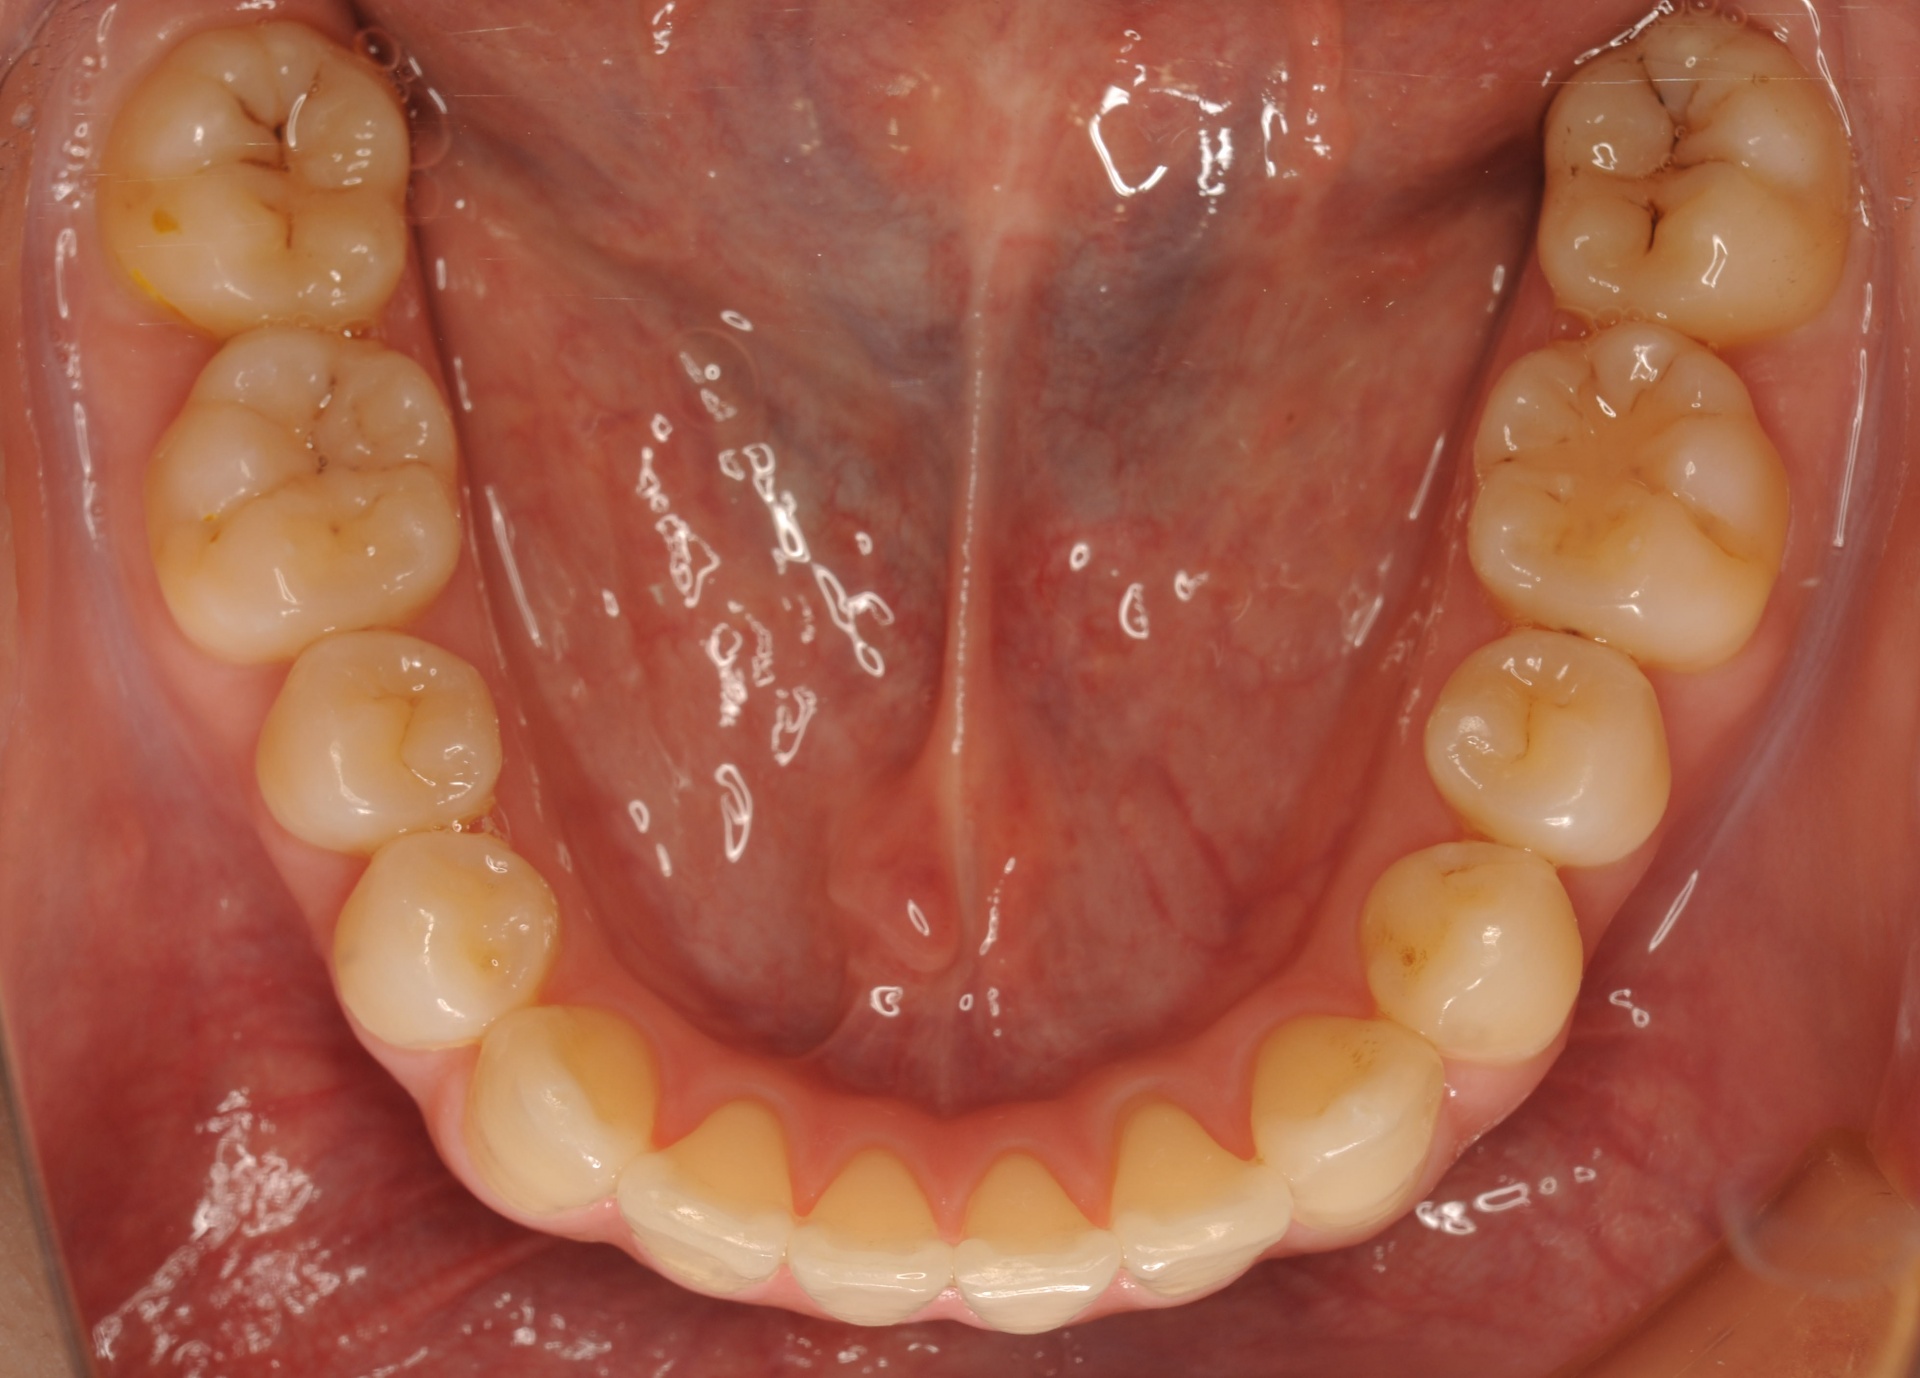

治療後

上下の正中は一致し、上顎両側犬歯は歯列内に誘導されました。奥歯の咬合関係は緊密で、再配列されたことにより機能・審美ともに改善されました。

| 治療内容 | 20代女性 上顎は叢生量が大きいため小臼歯抜歯のスペースを利用し、下顎は非抜歯で叢生を改善し各歯の再配列を行った |